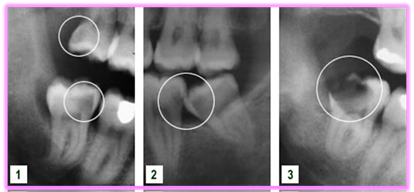

Då visdomständerna är de sista tänderna i bettet att eruptera är förekomsten av total eller partiell retention av visdomständer relativt vanligt. 72% av svenskarna i åldrarna 20 till 30 år har minst en retinerad visdomstand. De kan orsaka smärta, svullnad och infektion – och kan förstöra angränsande tänder och ben. Operativt avlägsnande av visdomständer är ett av de vanligaste kirurgiska ingreppen inom tandvården. Preoperativ bedömning av kirurgiska svårigheter är grundläggande för planeringen inför operativt avlägsnande av retinerade visdomständer. Vinsten av operationen ska alltid överstiga risken med ingreppet. Bedömningen är inte bara viktig för beslut om patienten ska remitteras till specialist eller inte, utan också för att informera patienten om eventuella risker och komplikationer i samband med det operativa ingreppet.

- Kron/rotresorption

- Retinerade tänder med associerade patologiska tillstånd (cystor, tumörer)